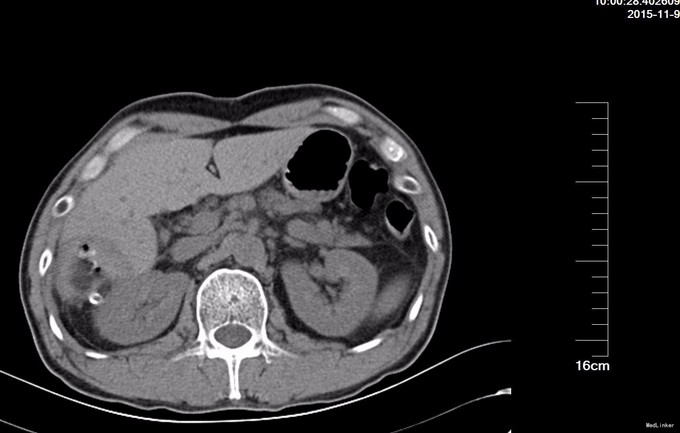

查体: 腹部平坦,未见胃肠型及蠕动波,未见腹壁静脉曲张,全腹软,无压痛,无反跳痛或腹肌紧张,未及腹部肿物,Murphy征阴性。肝脾肾区无叩击痛。移动性浊音阴性。肠鸣音4次/分。 辅查: BUS 提示肝脏大小属正常范围,肝内见多个高回声团,较大者位于右叶,大小约5.6x4.2cm,边界清。 门静脉主干直径约1.0cm。 肝内外胆管未见扩张。 胆囊大小约5.3x1.8cm,壁厚约0.2cm。 脾肋间厚约3.0cm。 胰腺大小、形态正常,主胰管未见扩张,胰腺未见明显占位性病变。

诊断: 肝血管瘤 治疗:全麻下腹腔镜探查,见胆囊无异常,右叶后下段2枚血管瘤,大者直径5.4厘米,外生性,小的直径3厘米,扁平状,左叶脏面可见2厘米扁平血管瘤,术中诊断肝多发血管瘤,2枚较小血管瘤直接腔镜下电烧消除,较大的肝血管瘤继续腔镜下包膜外剥脱。手术时间130分钟,术中失血500毫升。 术后病理,镜下见大小不等,形状不规则的血管,病理诊断:(肝右叶)海绵状血管瘤。

术后复查CT, 肝脏S4段及S6段可见两个低密度占位,与周围肝实质界限欠清,大小分别约25×16mm、51×48mm,前者边缘少量气泡;后者内可见气泡和少量稍高密度影,邻近导管外引流,周围脂肪间隙渗出改变。术后四天腹腔引流20毫升,予以拔除,病人出院。该血管瘤外生性,直径超过5厘米,尽管血管瘤恶变几率很低,但是肝血管瘤确实可以破裂出血,尤其像这样的外生性血管瘤。腔镜下切除肝血管瘤,由于控制出血比较可能,再加上容易破裂,总体上术中出血会比开腹多,手术时间也可能比开腹时间长,但是腹壁无大刀口,术后恢复确实比开腹手术快很多,保守估计,术后至出院时间比开腹手术的缩短1倍,患者受益,值得开展。